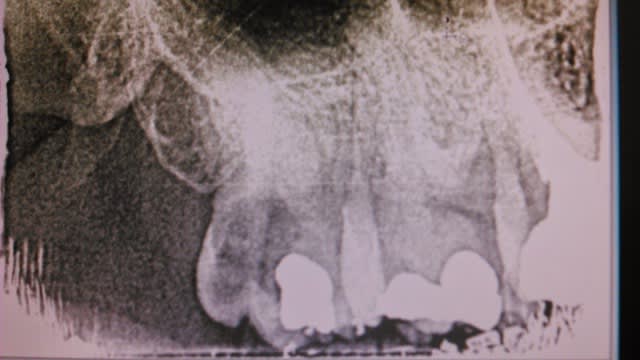

transplant chez un jeune de 19 ans je crois

contrôle à 6 mois